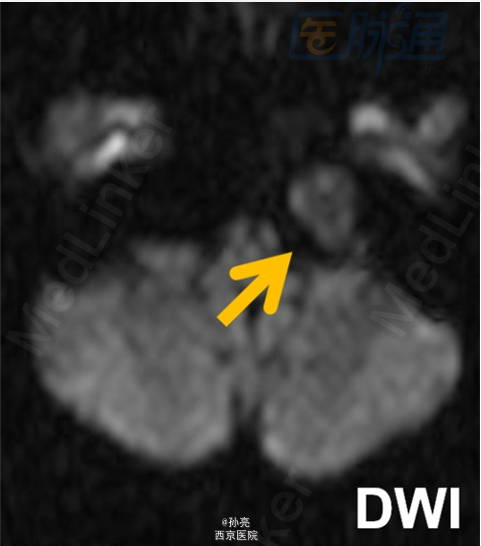

50岁男性,长期左侧耳聋。

CT检查多表现为颞骨岩尖部出现边界清楚的囊性膨胀性病变(图A箭头)。由于包块内血液分解产物和蛋白质碎片的积累,其在MRI检查时,多表现为T1和T2加权图像上的高信号影(图B箭头)。在MRI的T2加权图像上,可见到包块的周围有明显的低信号影包绕。而这主要是由含铁血黄素在局部的沉积所致(图C箭头)。此外,包块多无扩散受限(图D箭头)。

该疾病主要的鉴别诊断可能包括含水较多的粘液囊肿,及伴有血栓形成的颈内动脉动脉瘤等。